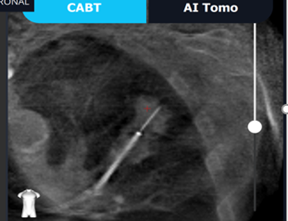

De softwarebehandlede CT-billeder med ruten og markeringen af læsionen sammenholdes med de real time billeder som dannes forud for proceduren med patienten på lejet. Fluoroskopet roteres omkring patienten, og systemet vil herefter omdanne gennemlysningsbillederne til CT-lignende rekonstruktioner – den såkaldte C-arm based tomography (CABT).

Figur 5: Rekonstruerede CT-lignende optagelser (CABT)